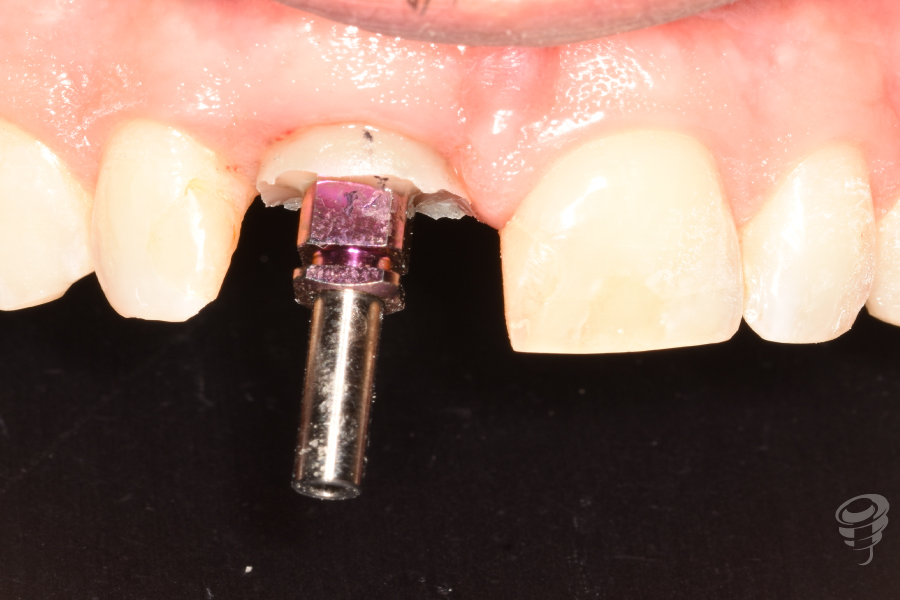

Fase 1: Cirugía (Dia 0)

- Extracción atraumática del diente 11 con periotomos y luxadores.

- Colocación del implante: Implante cónico de titanio grado IV (IPX 4012) con torque de inserción de 40 Ncm. Posición: 3mm apical al CEN del diente adyacente, 2mm palatino a la tabla vestibular.